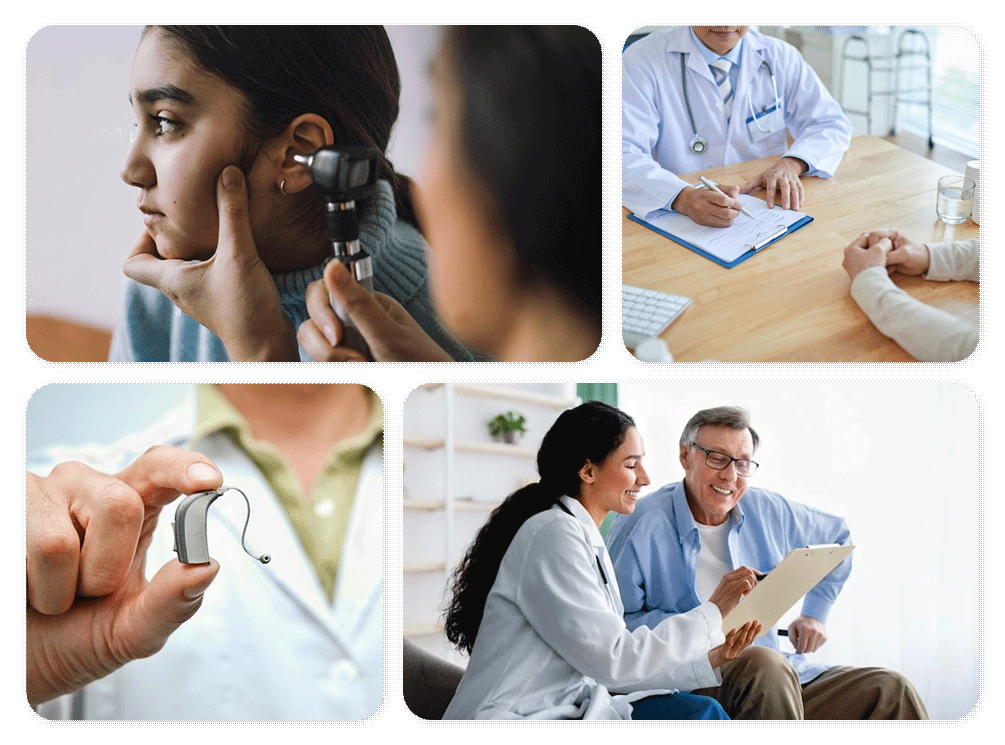

Better Hearing in 4 Steps

From Detection to Thriving Sound Experience.

Detecting Auditory Issues

Recognize signs of hearing problems and take proactive steps.

Expert Consultation

Book a consultation with Aideo Hearing professionals to diagnose and understand your unique needs.

Personalized Solutions

Find the perfect fix based on your diagnosis for improved hearing.

Thriving with Aftercare Support

Enjoy life's sounds anew with ongoing assistance and care. Aideo Hearing, a hearing partner for Life.

Hearing Assessments

Thorough evaluations to understand your unique hearing profile, guiding personalized solutions for you.

Expert Audiologists

Professional guidance through every step, from diagnosis to selecting the perfect hearing aid for you.

Advanced Hearing Aids

Precision fittings ensure maximum comfort and performance, bringing clear sound back to your life.

Tailored Hearing Solutions

Customized solutions catered to your lifestyle, ensuring seamless integration and optimal hearing experiences.

Personalisation and Maintenance

Ongoing fine-tuning and support to keep your hearing aid working at its best, always.

Best After Care Services

Empowering you with knowledge and techniques to enhance your hearing wellness journey.